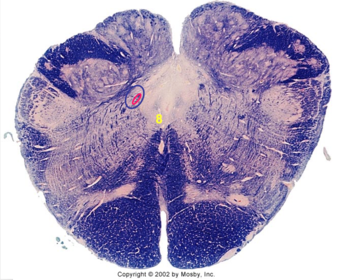

| Spinal tract of V | |

| Spinal nucleus of V | |

| Medial vestibular nucleus | |

| Inferior vestibular nucleus | |

| Dorsal cochlear nucleus | |

| Ventral cochlear nucleus | |

| Inferior olivary complex | |

| Inferior cerebellar peduncle | |

| CN IX | |

| Anterior spinocerebellar tract | |

| Central tegmental tract | |

| Olivary internal arcuate fibers | |

| Solitary tract | |

| Abducens root fibers | |

| Longitudinal pontine fibers (corticospinal tract) | |

| Transverse pontine fibers (dark fibers) | |

| Pontine nuclei (pale) | |

| Medial lemniscus | |

| ALS | |

| Trapezoid body | |

| Ventral trigeminothalamic tract | |

| Superior olive | |